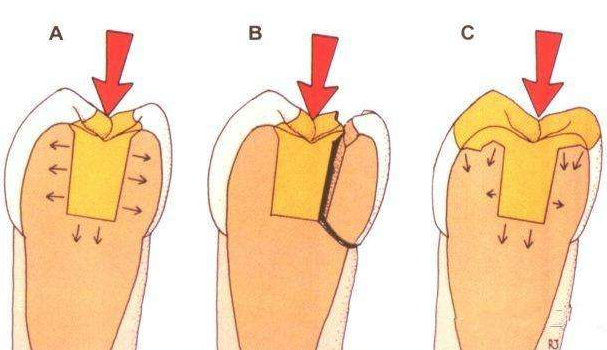

专业一点来说就是,嵌体是一种嵌入牙体内部,用以恢复牙体缺损的形态和功能的修复体。

嵌体是为牙齿量身定做的修复体,通过黏合剂将其黏在有缺损的牙齿上,由于嵌体在形态、硬度等各方面与牙齿吻合度很好,这样不仅解决了牙齿缺失部分容易变大的难题,也减轻了患者频繁补牙的痛苦。

1、牙合面形态与对牙合牙高度协调。因为瓷嵌体是在模型上做的,可以360°全方位吻合牙缺损,高度效仿原牙的凹凸咬合关系,牙体预备量较少,能够保持牙齿外形的完整,减少牙髓牙周刺激,保留更多的牙体组织。

2、嵌体的整个的制作过程中完全避免了在口腔内部操作的干扰因素,这就使得嵌体的制作比传统的补牙要更精细。

3、边缘密合性高。边缘密合性好、咀嚼备感舒适,避免了传统补牙容易脱落、嵌塞食物并造成继发龋等问题。这一点取决于牙医的操作技术和牙科技师的制作水平。